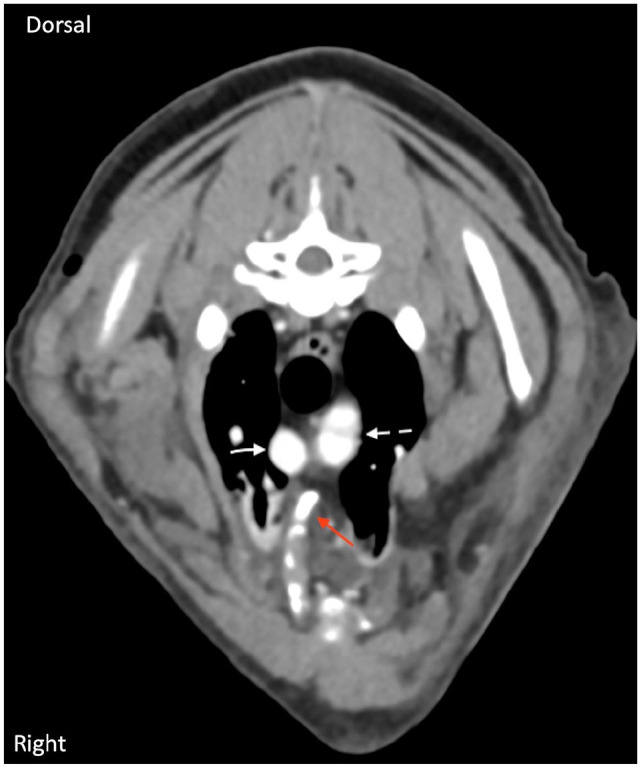

病例总结:一只11岁的雄性绝育家长毛猫在被狗袭击后胸部严重受伤,被送到紧急转诊医院。最初的稳定包括补充氧气、静脉输液、即时超声(POCUS)、连续血气分析、胸部和腹部x光片、阿片类镇痛药和广谱抗生素。CT显示多发内移位肋骨骨折,穿透纵隔,靠近颅腔静脉和主动脉弓近端。采用视频辅助胸腔镜手术(VATS),在2.7 mm 0°短腹腔镜下,经皮缝合放置特制玻璃纤维夹板,准确复位肋骨骨折碎片,避免进一步损伤胸内结构。夹板固定了6周。在第8周复查时,猫没有心血管或呼吸损伤的迹象,能够恢复正常活动。术后14个月进行长期随访电话随访。业主报告说,病人一直很好,没有任何并发症。相关性和新信息:据作者所知,这是第一个使用VATS治疗猫创伤性肋骨骨折的报道。本病例强调了该方法的可行性和成功,是未来临床病例的可行选择。

Case summary: An 11-year-old male neutered domestic longhair cat was presented to an emergency referral hospital after sustaining severe injuries isolated to the thorax after a dog attack. Initial stabilisation included oxygen supplementation, intravenous fluid therapy, point-of-care ultrasound (POCUS), serial blood gas analyses, thoracic and abdominal radiographs, opioid analgesics and broad-spectrum antibiotics. CT revealed multiple internally displaced rib fractures that punctured through the mediastinum and were in intimate proximity to the cranial vena cava and proximal aortic arch. Video-assisted thoracoscopic surgery (VATS) was performed using a 2.7 mm 0° short laparoscope to place a custom-made fibre glass splint via percutaneous suturing to accurately reduce the rib fracture fragments without further damage to the intrathoracic structures. The splint remained in place for 6 weeks. At the 8-week recheck, the cat had no evidence of cardiovascular or respiratory compromise and was able to resume normal activity. A long-term follow-up phone call was conducted at 14 months postoperatively. The owner reported that the patient has continued to do well without any complications.